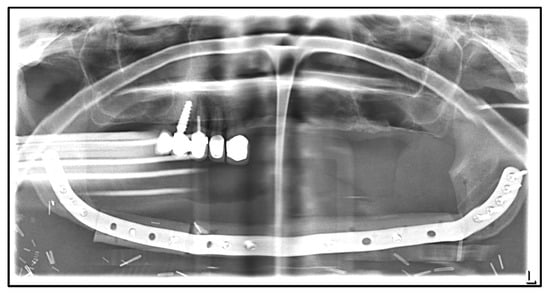

| Date | Intervention |

|---|---|

| 2016: | Diagnosis of breast cancer with osseous metastasis. Mammectomy, adjuvant radiation, and intravenous bisphosphonate therapy with zoledronate 4 mg every 6 months (2016–January 2019). |

| 2019: | Extraction of the lower left canine and first premolar due to intraoral pus leakage by the general dentist. |

| January 2020: | Admission to hospital with MRONJ of the left mandible and recurrent fistulation/pus leakage. |

| April 2020: | Partial mandibular resection from the left to the right mandibular angle, CAD/CAM-assisted reconstruction using a free fibular graft and PSI, temporary tracheostomy. In the course: development of aspiration pneumonia treated with piperacillin and tazobactam 4.5 g for 8 days. |

| April 2021: | Placement of four dental implants in the neo-mandible for dental rehabilitation. |

| August 2021: | Surgical removal of the upper right incisor, smoothening of the bone, primary wound closure, perioperative antibiosis with ampicillin and sulbactam |